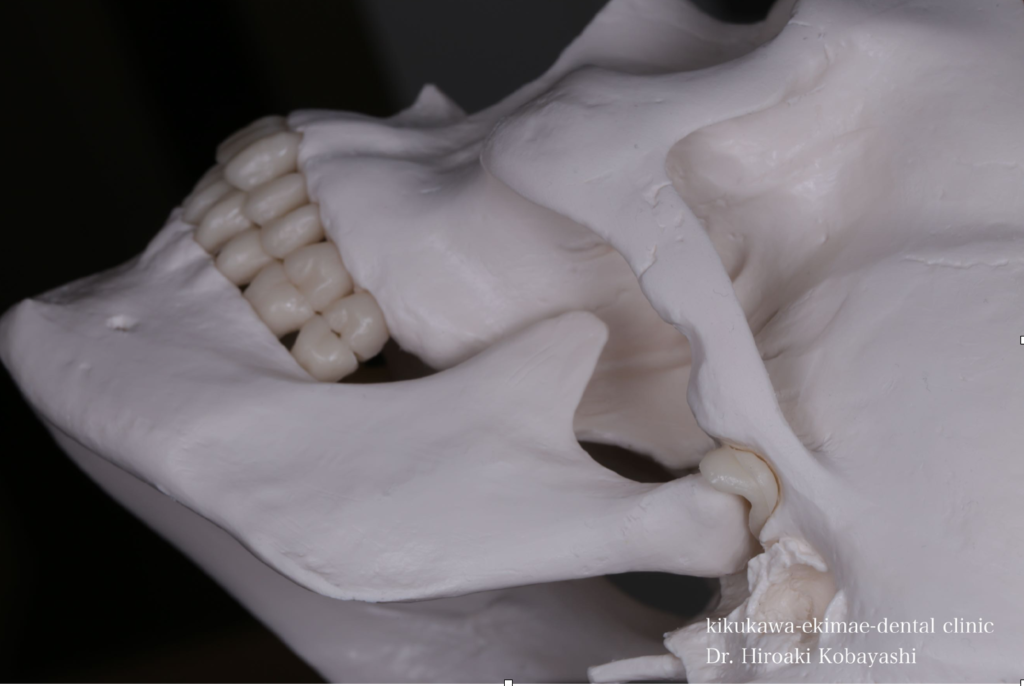

精密根管治療とは?歯を残すために本当に大切な選択

「できるだけ歯を抜きたくない」「何度も同じ歯が痛くなる」「根の治療をしたのに治らない」

このようなお悩みをお持ちの方にこそ知っていただきたいのが、精密根管治療です。

根管治療とは、虫歯が神経まで達した場合や、過去に治療…